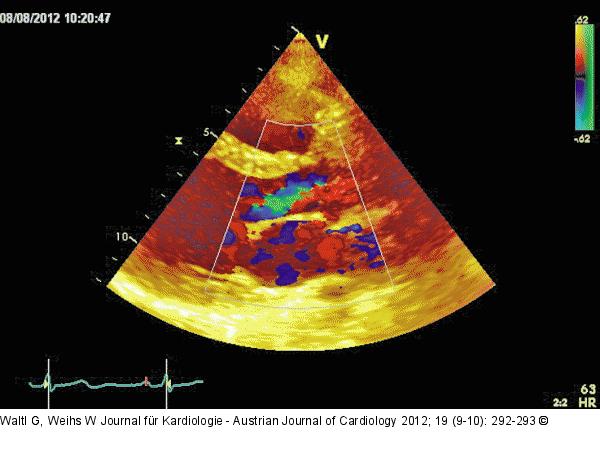

Abbildung 2: Parasternaler Längsschnitt Parasternaler Längsschnitt mit Farbdoppler: Aorteninsuffizienz mit schmalem Jet (Vena contracta < 0,3 cm, < 25 % des LVOT). |

Parasternaler Längsschnitt mit Farbdoppler: Aorteninsuffizienz mit schmalem Jet (Vena contracta < 0,3 cm, < 25 % des LVOT). |